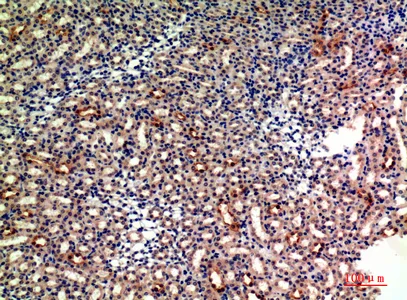

P-Selectin Rabbit Polyclonal Antibody

Cat: APRab16595

Size1:50μl Price1:$118

Size2:100μl Price2:$220

Size3:500μl Price3:$980

Size2:100μl Price2:$220

Size3:500μl Price3:$980